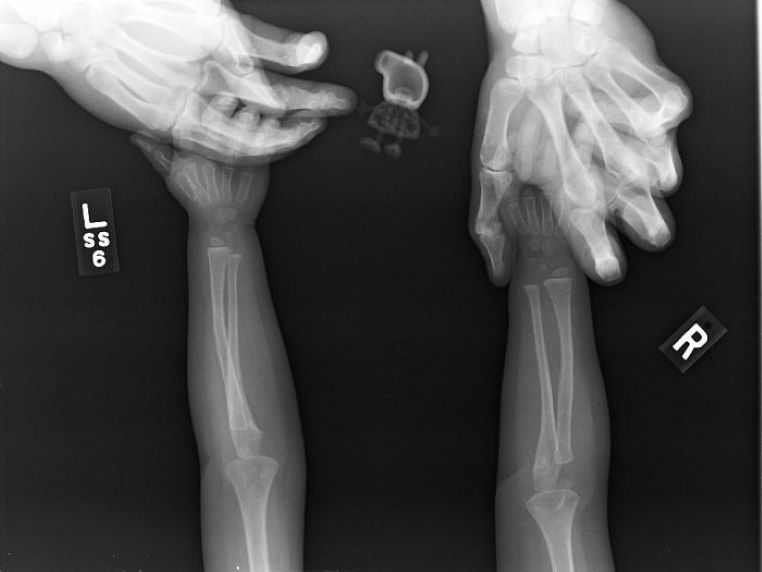

Quand une petite fille demande à son père de passer la radio avec elle…

galerie-rayon-x-radio-papa-fille